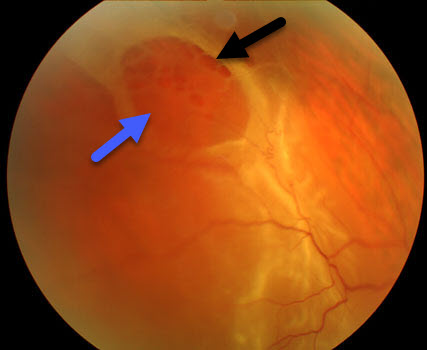

The retina lines the inside of the eye like wallpaper. It has multiple layers that are normally stuck together. Degenerative retinoschisis is an age-related disorder where these layers split.

Virtually all patients with degenerative retinoschisis are completely asymptomatic. The retinal splitting, which may be in one or both eyes, is detected by your eye doctor during a dilated retinal examination as a smooth solid retinal elevation.

Almost all patients with degenerative retinoschisis need no treatment since the retinal splitting does not usually progress. Rarely patients can develop holes within the split tissue that can mimic or cause a retinal detachment. Patients are usually examined every 6 to 12 months. New flashes, floaters or painless side vision loss are symptoms of a retinal detachment and need to be examined immediately.